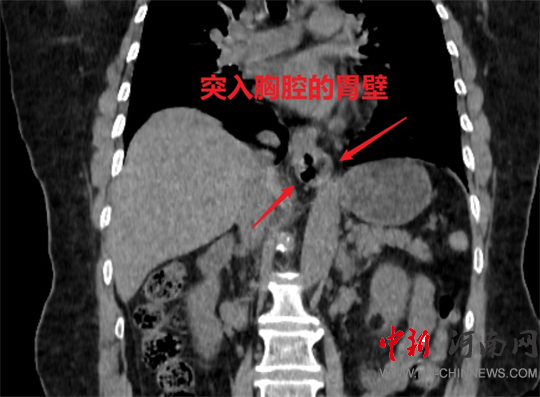

食管裂孔疝是指腹腔內(nèi)的臟器(主要是胃,也包括小腸和大網(wǎng)膜等)通過人體的膈肌食管裂孔進入胸腔所導致的疾病。

食管裂孔疝患者會有燒心、反酸、噯氣、胸痛、吞咽困難等相關(guān)癥狀,以及會出現(xiàn)出血、反流性食管狹窄、疝囊嵌頓等相關(guān)并發(fā)癥;胸腔內(nèi)的臟器如心臟、肺、縱隔等可能受到疝囊的壓迫,還會產(chǎn)生氣急、心悸、咳嗽、發(fā)紺等癥狀。

傳統(tǒng)食管裂孔疝修補術(shù),通常需要開腹或開胸手術(shù),切口長、創(chuàng)傷大、住院時間久。而腹腔鏡下食管裂孔疝修補術(shù)的創(chuàng)面小,且具有對心肺功能影響小、術(shù)后恢復快、復發(fā)率低等優(yōu)點。

當患者出現(xiàn)反酸、燒心等癥狀時,部分患者可以選擇藥物治療。但當不適癥狀持續(xù)不緩解,或者經(jīng)過藥物治療后效果不明顯,應(yīng)考慮及時行手術(shù)。

安全有效的微創(chuàng)手術(shù)方式之一

這種手術(shù)方式

通過腹腔將進入胸腔的臟器

拉入原來的位置

減少了開胸手術(shù)的創(chuàng)傷

同時行胃底折疊術(shù)

進一步起到抗食管返流的作用

可減少患者術(shù)后反酸

燒心等不適癥狀